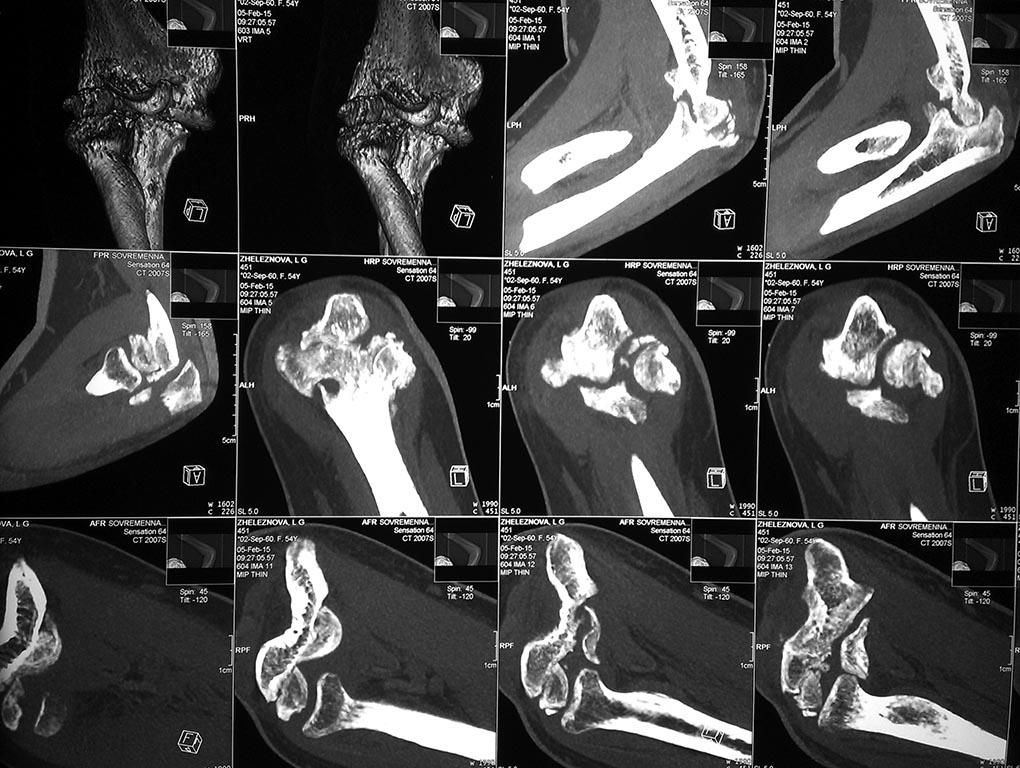

У женщины 54 лет имеются последствия закрытого вывиха костей предплечья...

Травма 08.11.14 г., окончательное вправление лишь 10.11.14 г., тогда же появились признаки нейропатии локтевого нерва, они остаются до сих пор.Движения в суставе качательные, практически анкилоз в положении 90 град.

Снимки КТ в приложении.